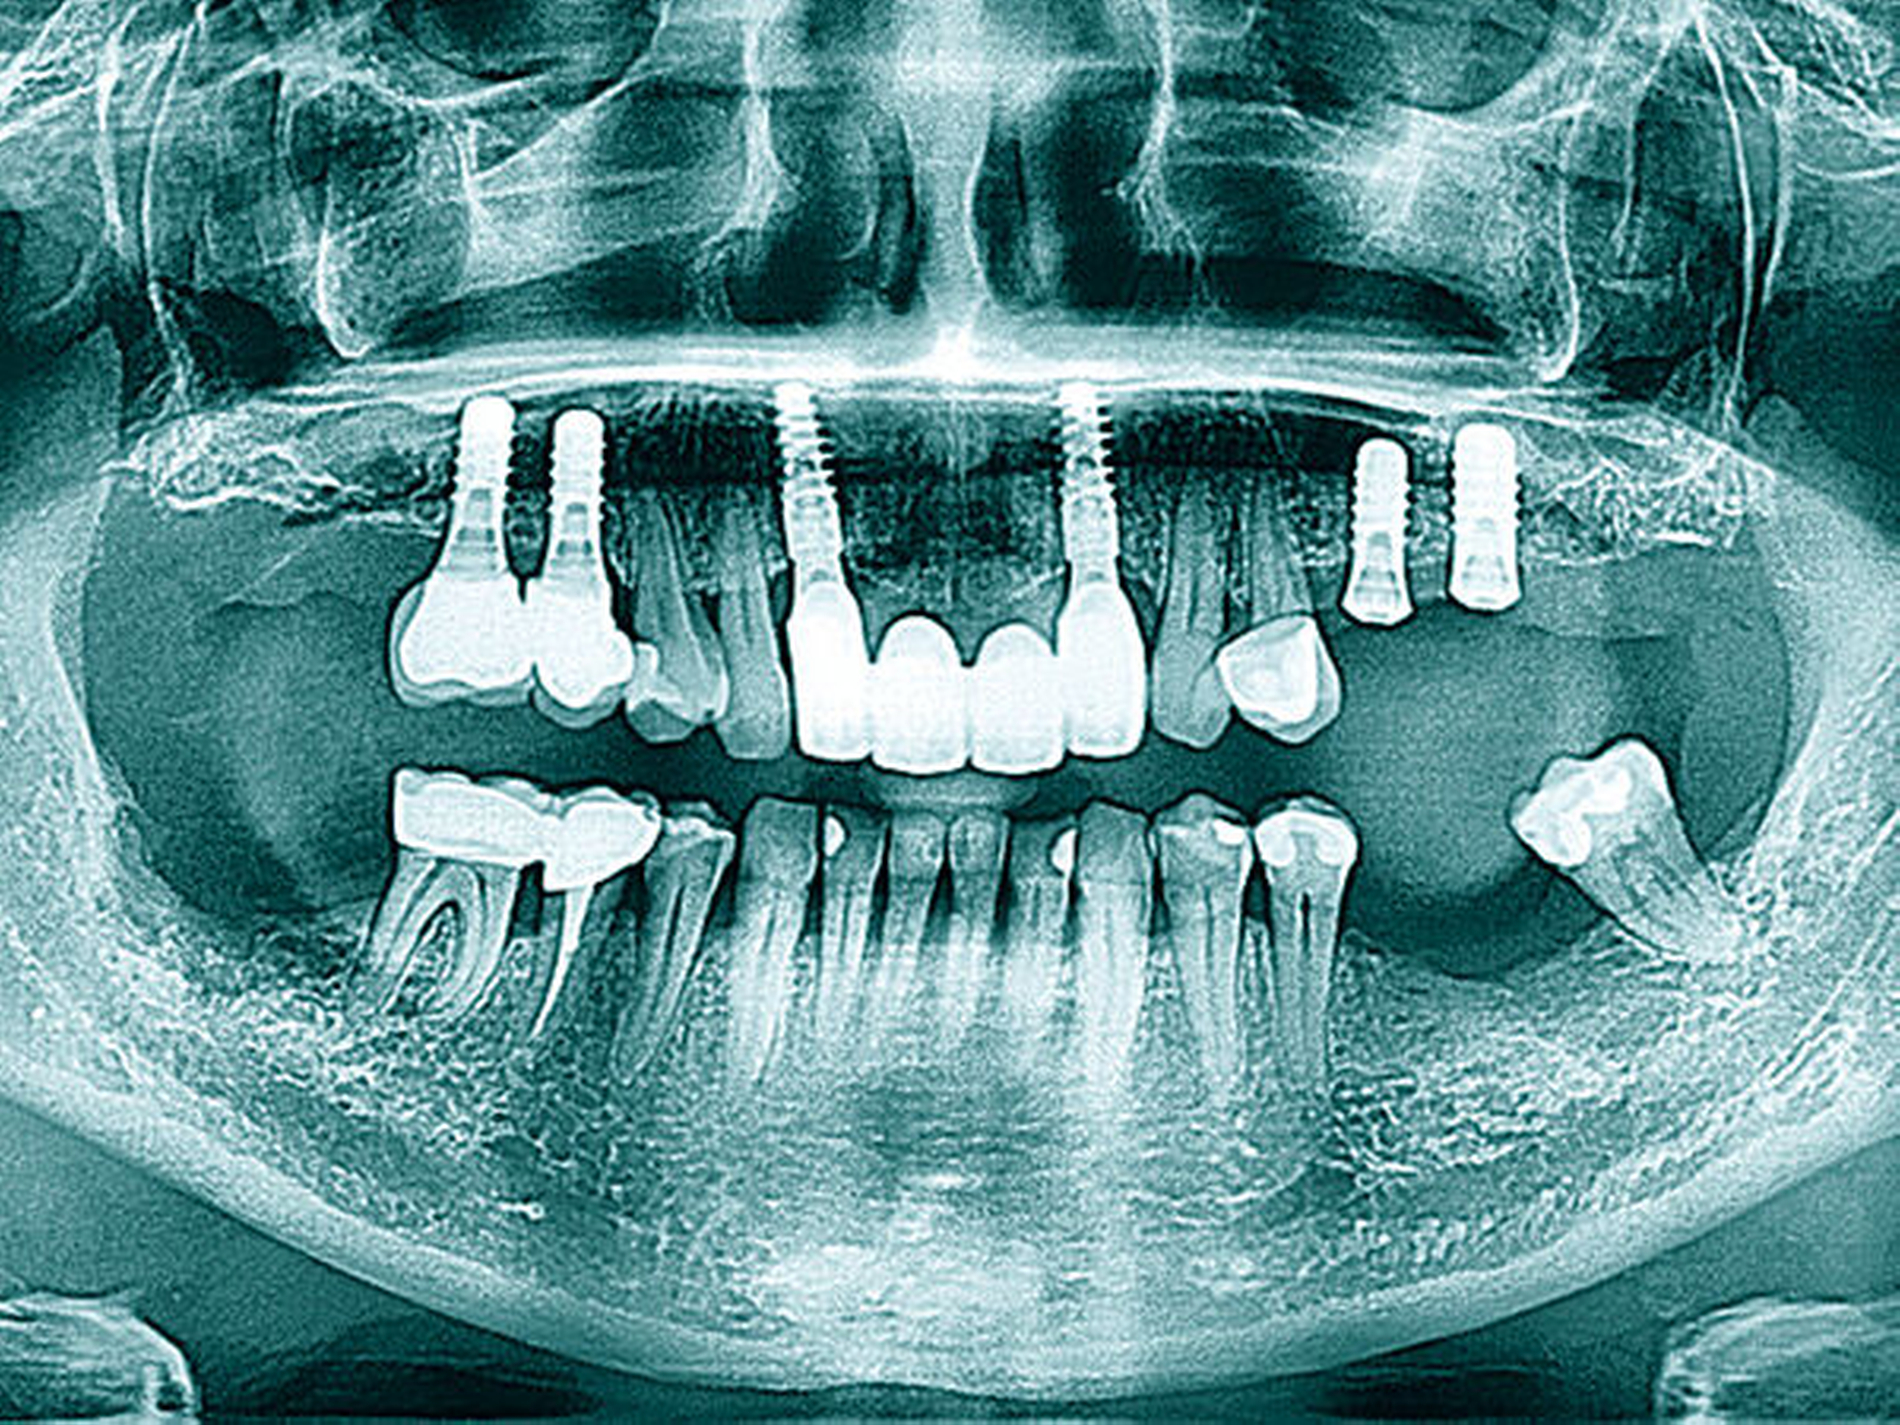

In den Abbildungen 6 bis 9 sind mehrere Fälle mit langem Beobachtungszeitraum dargestellt. Beachtenswert ist vor allem der zu beobachtende vollständige Umbau des Knochens inklusive der Ausbildung einer neuen Kompakta. Die augmentierten Bereiche sind nach wenigen Jahren nicht mehr als solche zu erkennen. Die Arbeit mit autologem Knochen ist insbesondere für die Patientengruppe interessant, die bevorzugt nach biologisch sicher verträglichen Behandlungen sucht. Dieser Trend nimmt unseren Beobachtungen nach stetig zu. n